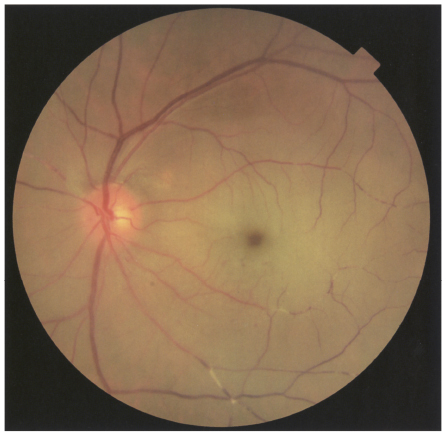

左眼の眼底写真を別に示す。

- 眼底写真あり→ cherry red spotが典型的所見!

| 所見 | Cherry red spot(網膜虚血により黄斑だけ赤く見える) |

- 網膜は虚血で白く濁るが、黄斑中心窩は薄く虚血の影響を受けにくい

→ 背景の脈絡膜の血流が透けて赤く見える

→ これが “さくらんぼ様紅斑”

- 🍒 特徴的なのが「Cherry red spot」=黄斑部だけ赤く見えるやつ。